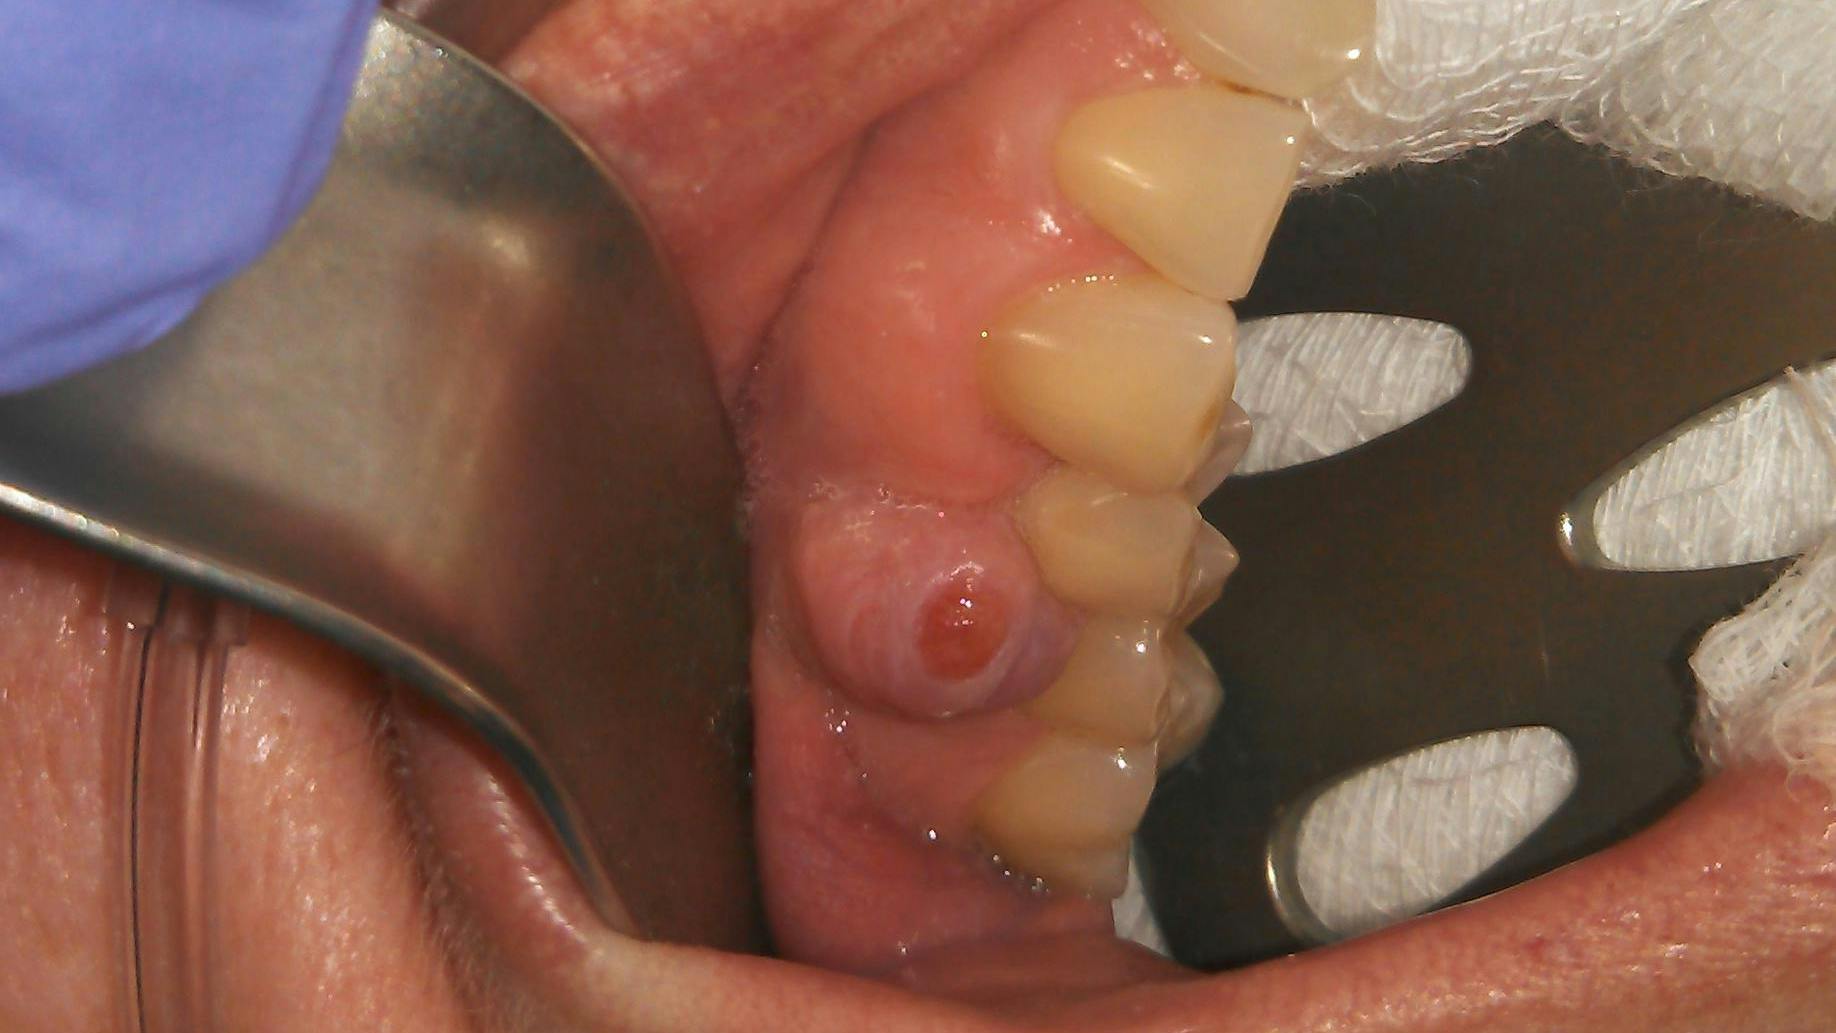

A 50-year-old female presented for a new-patient exam upon the recommendation of her general practitioner. Her chief complaint: “My doctor said that I have an infection on one of my top right teeth.” She pointed to a raised tissue mass between teeth nos. 4 and 5.

Clinical assessment revealed a 6 mm pink, raised, firm mass of osseous tissue measuring 12x12 mm. It was not tender to palpation and did not bleed easily when manipulated (figures 1 and 2). Radiographic assessment was within normal limits (figure 3).